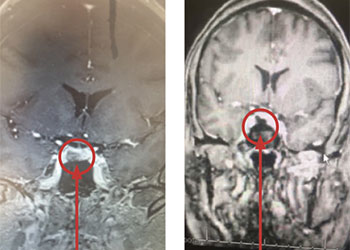

Brain:

Pituitary Tumor with Cushing’s Disease

Author: Michael Brisman M.D., F.A.C.S., Read More!